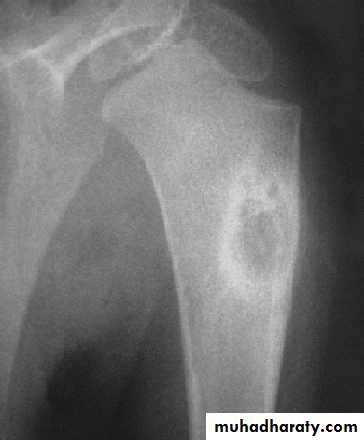

Developmental disorder whereby normal bone is replaced by fibrous tissue with flecks of osteoid.It may affect one bone (monostotic) or multiple bones (polystotic).

The lesion may be very large causes bone expansion and cortical thinning with progressive deformity and sometimes pathological fracture.Lesions occur in metaphysis & diaphysis, proximal femur is a common site it gives characteristic deformity called (shepherd’s-crock deformity(عصا الراعي.

X-ray shows lucent cystic lesion sometimes large and multilocular with bone expansion and cortical thinning it contains multiple calcific spots giving the ground-glass appearance, there is always possible deformity or pathological fracture.